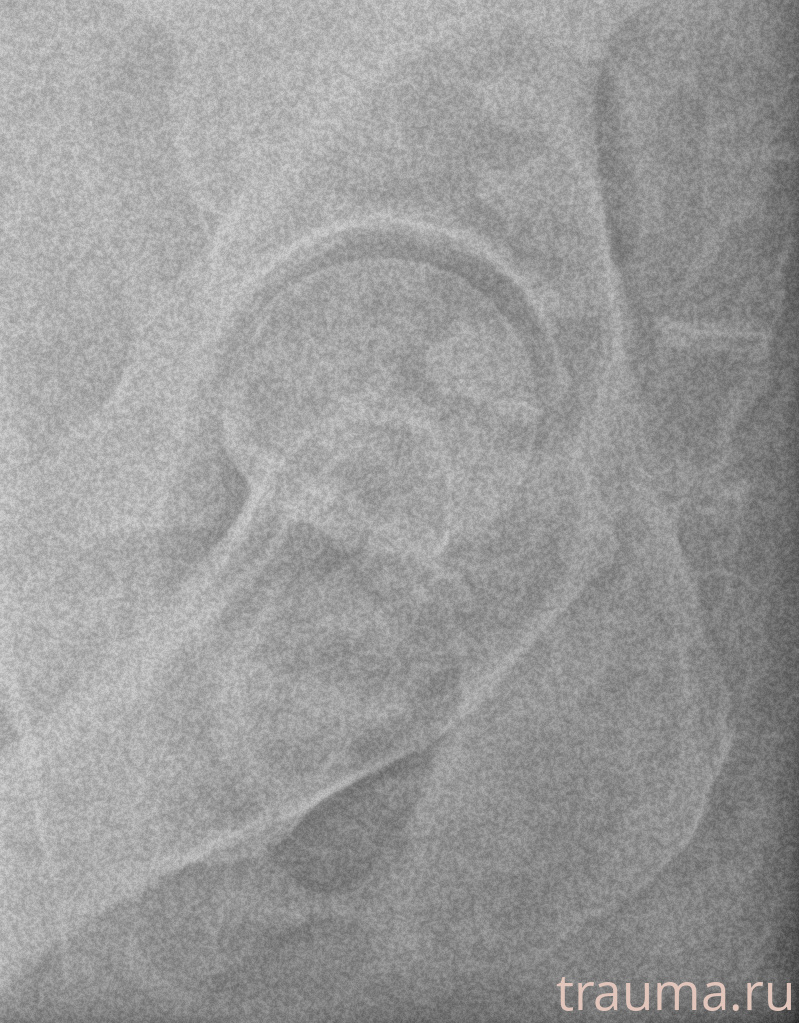

Рентген на дому: по вашему адресу приезжает врач-рентгенолог, травматолог-ортопед с мобильным рентгеновским аппаратом, проводит диагностику травмы или заболевания, делает необходимые рентгенограммы, дает рекомендации по дальнейшему лечению. Получить качественные снимки в домашних условиях возможно благодаря уникальной методике, разработанной МосРентген Центром для института  Склифосовского